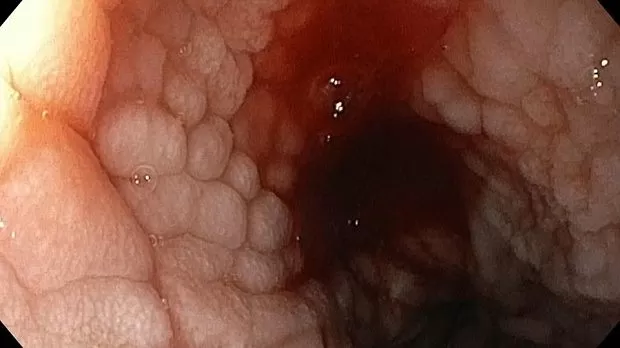

Публикации из социальных сетей: “Cobblestone esophagitis” (эзофагит со слизистой булыжной мостовой)

“Cobblestone esophagitis” (эзофагит со слизистой булыжной мостовой) - редкая эндоскопическая находка и ассоциируется с эозинофильным эзофагитом, кандидозом и пищеводом Барретта у взрослых. Он также может быть найден при тяжелом рефлюкс-эзофагите, вторичен к дистальной обструкции гастроинтестинального тракта. В нашем случае - это пациент после с 9-летним стажем бандажирования кардиального отдела желудка, признаками дуоденостаза, фундальной эрозивной гастропатией, расширением пищевода и уровнем жидкости в нем при горизонтальном положении, грыжи ПОД, эрозивно-язвенном дистальном эзофагите.. Пациент просто пришел удалить полип в прямой кишке и заодно посмотреть, что творится в желудке.... Ацетообеление+NBI+биопсия. ИПП на 3-4 мес и повтор для решения о Барретте.